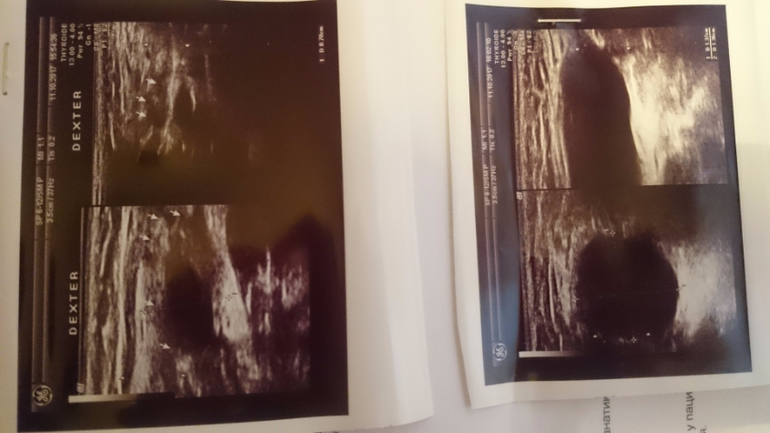

Сегодня сделали УЗИ: Сообщающаяся водянка семенного канатика. Левосторонний паховый лимфаденит

Прикрепляю фото